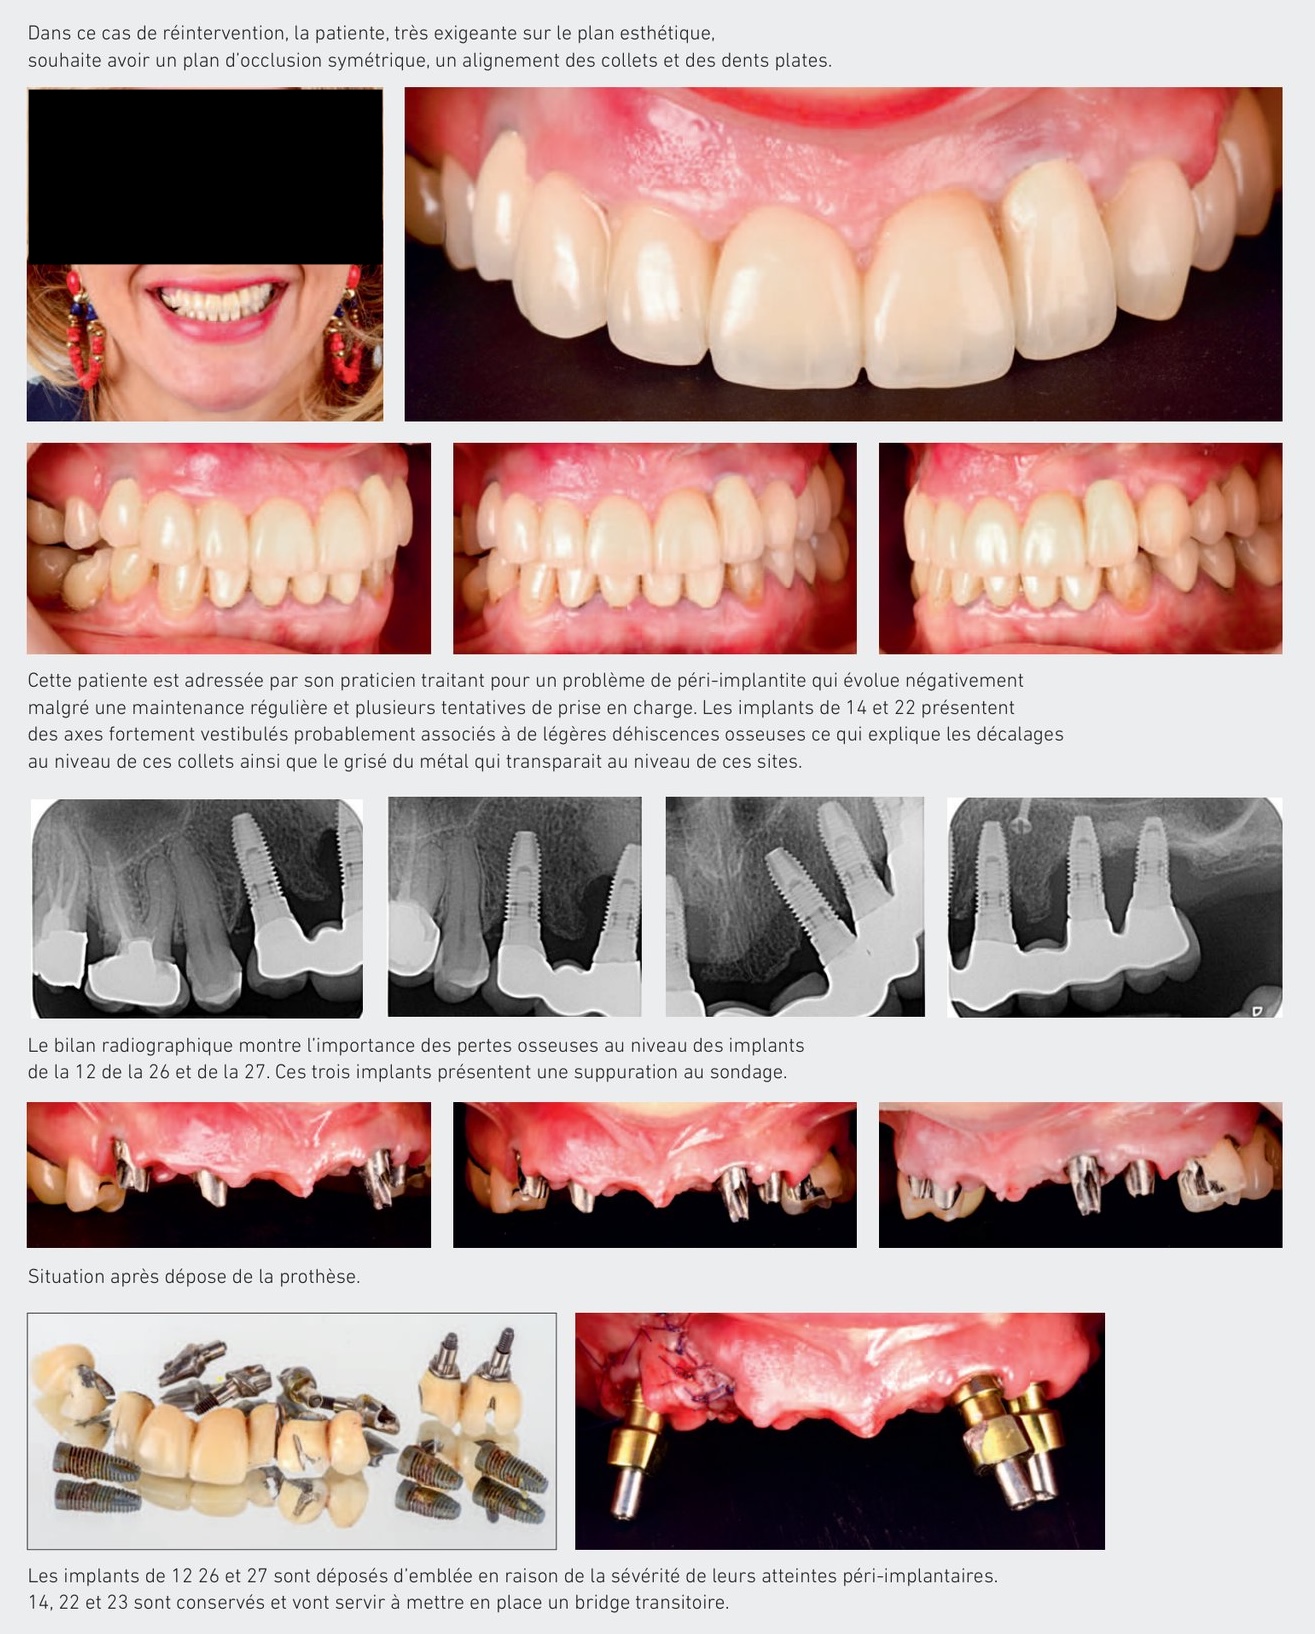

Dans ce cas de réintervention, la patiente, très exigeante sur le plan esthétique, souhaite avoir un plan d'occlusion symétrique, un alignement des collets et des dents plates.

Cette patiente est adressée par son praticien traitant pour un problème de péri-implantite qui évolue négativement malgré une maintenance régulière et plusieurs tentatives de prise en charge. Les implants de 14 et 22 présentent des axes fortement vestibulés probablement associés à de légères déhiscences osseuses ce qui explique les décalages au niveau de ces collets ainsi que le grisé du métal qui transparait au niveau de ces sites. Le bilan radiographique montre l'importance des pertes osseuses au niveau des implants de la 12 de la 26 et de la 27. Ces trois implants présentent une suppuration au sondage.

Les implants de 12 26 et 27 sont déposés d'emblée en raison de la sévérité de leurs atteintes péri-implantaires. 14, 22 et 23 sont conservés et vont servir à mettre en place un bridge transitoire.